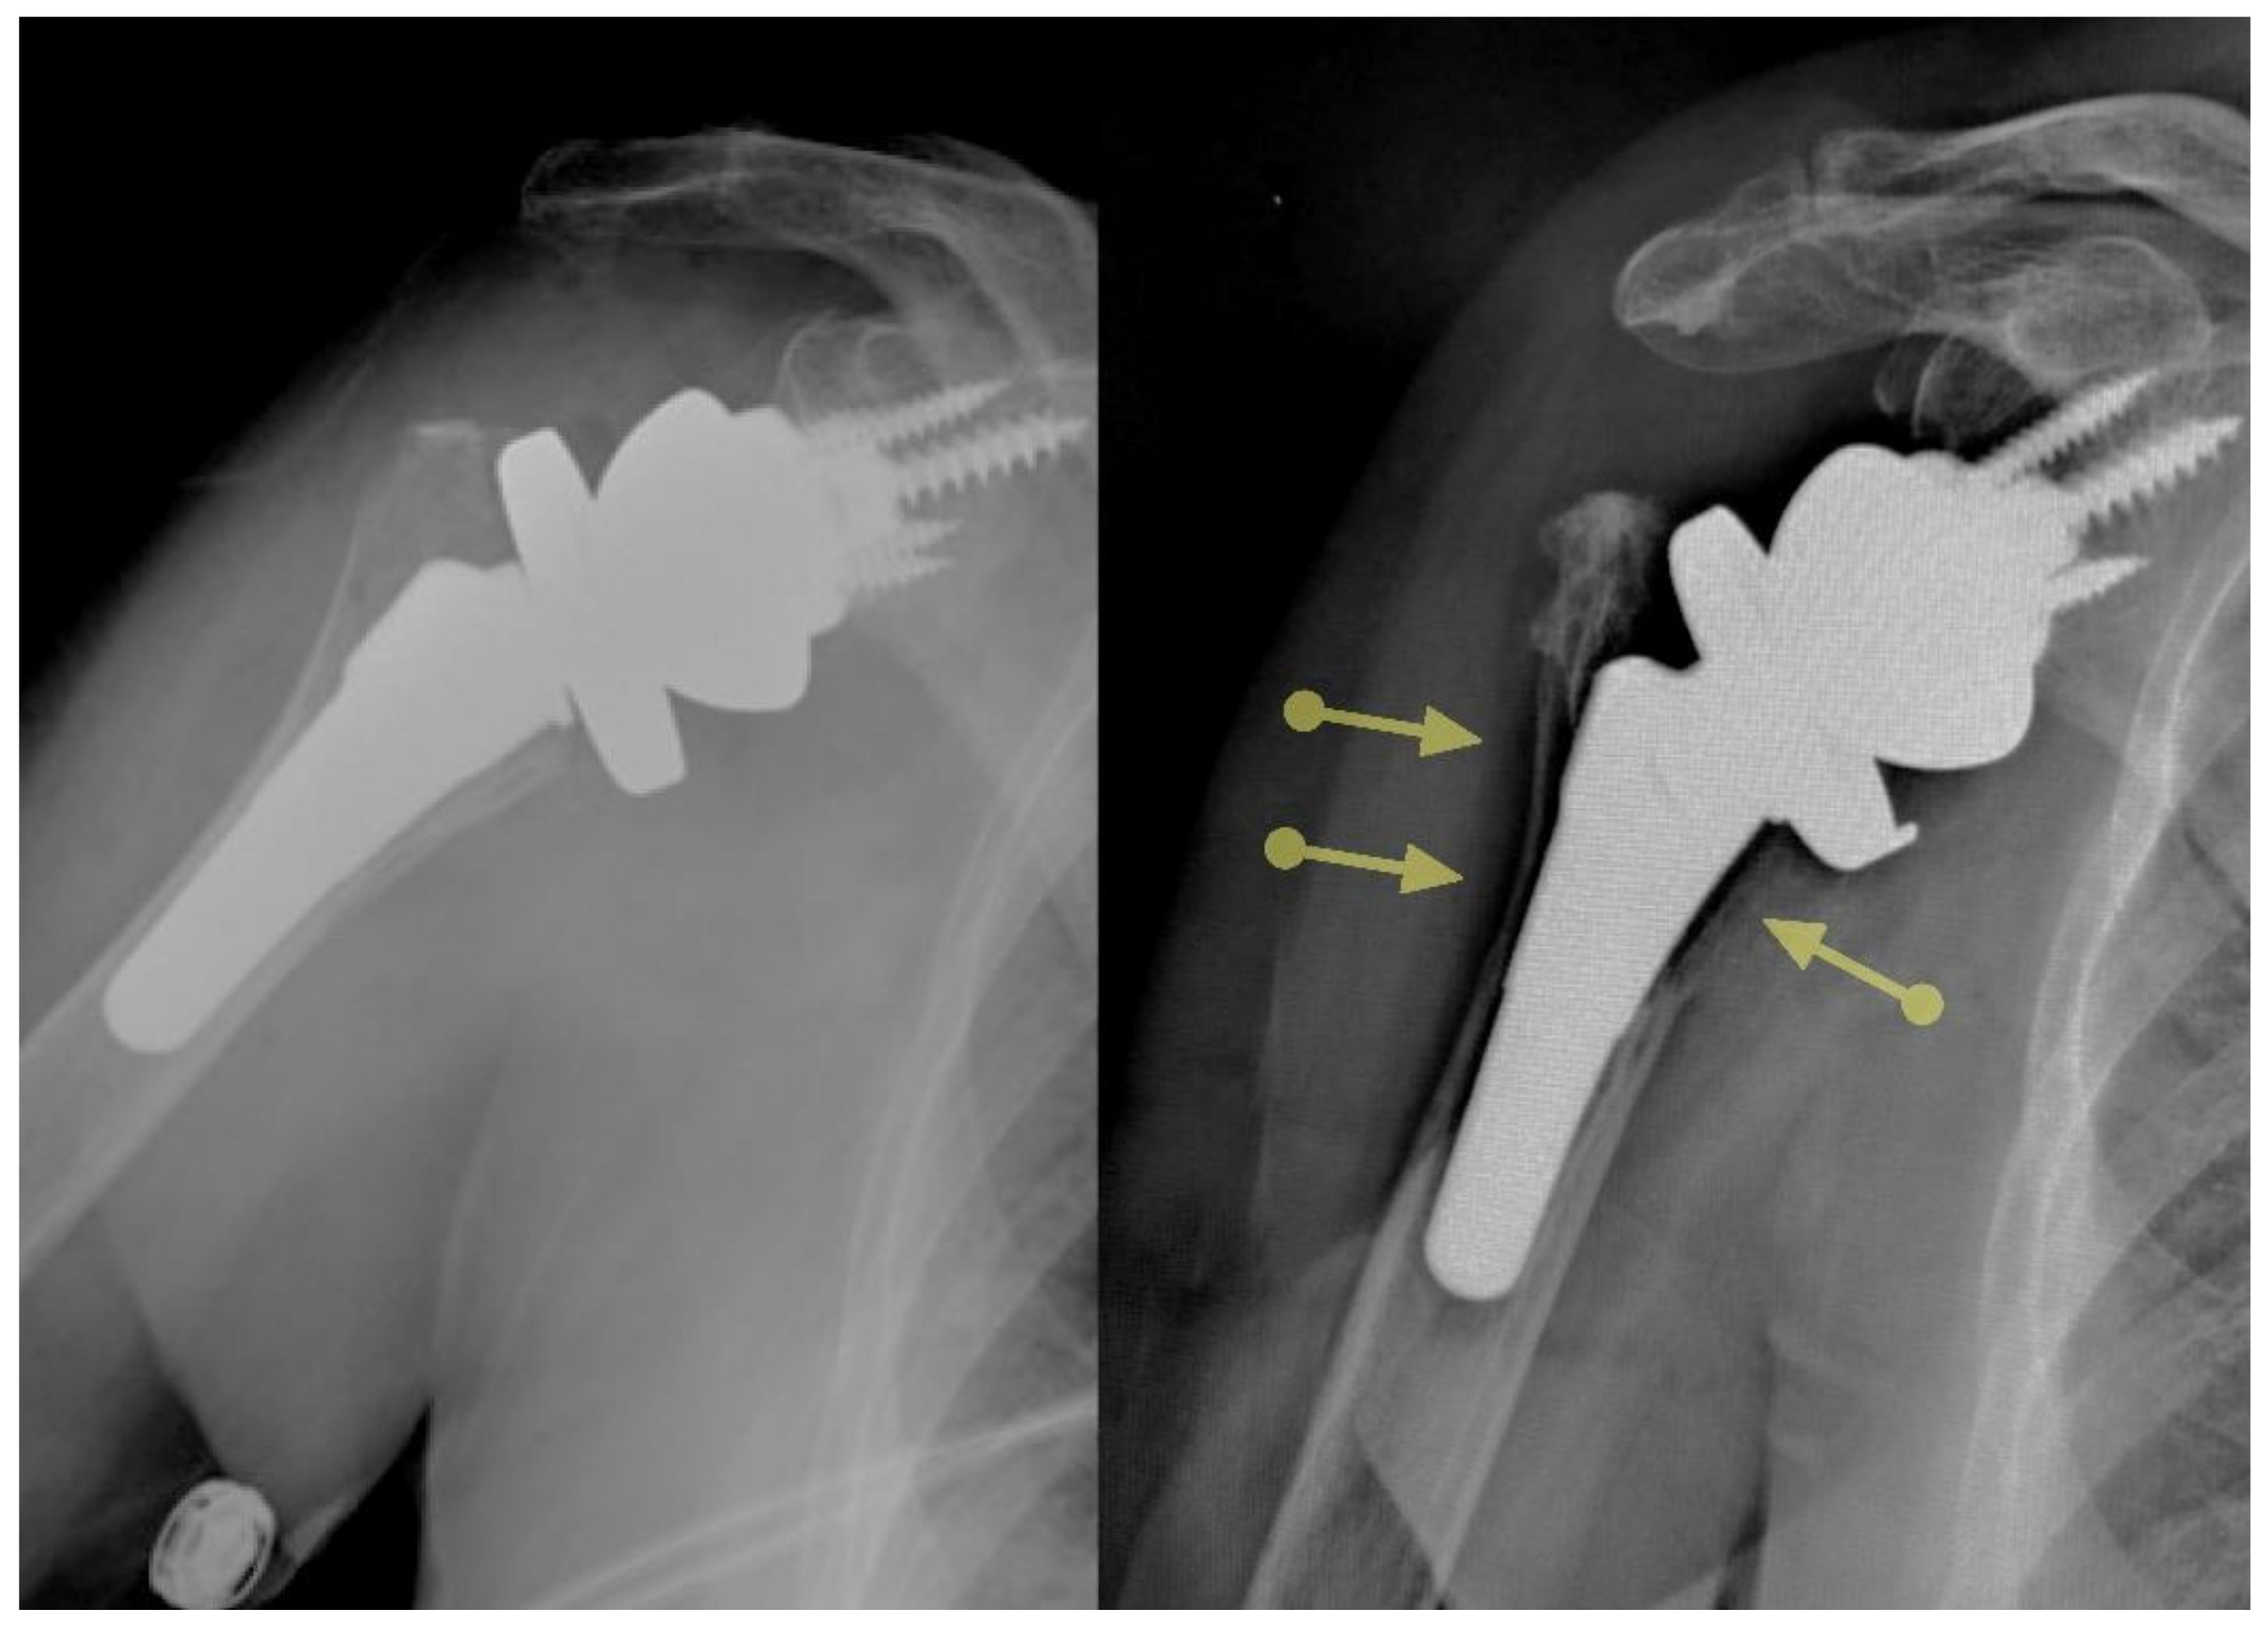

Certain ultrashort stems need larger diameters to achieve primary stability in the absence of diaphyseal contact. This concept has been captured with the fill–fit ratio popularized by Walch et al. [18]. Severe stress shielding with resorption of the greater tuberosity, and in extreme cases in areas of complete cortical defect, has been reported with the implantation of larger sizes of certain stems, and malalignment may accentuate these adverse bone reactions through point contact of the stem on the cortical bone, further shielding the proximal bone from stress (Figure 2). Thus, it is important to design implants that do not shield the metaphysis from stress.

Figure 2.

Certain ultrashort stems are associated with substantial stress shielding.